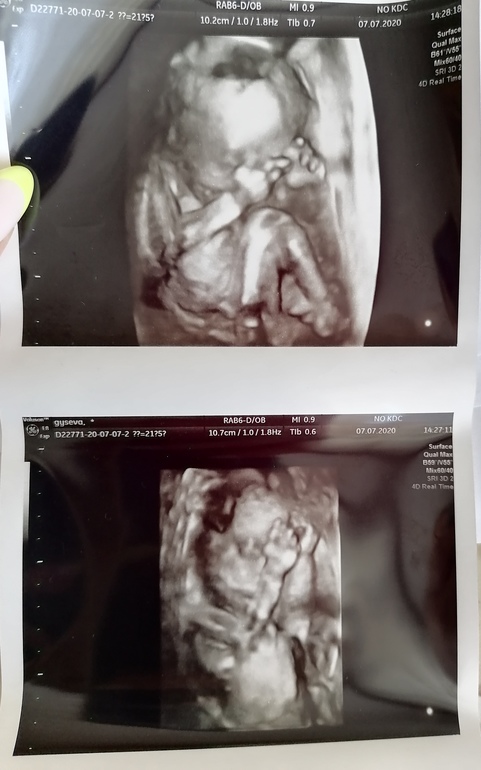

Наконец - то узнали пол нашего малыша+3д фото

Смело окрасила кружочек в розовый цвет, как мы и хотели, у нас будет девочка❣️На втором скрининге мне вообще ничего толком не сказали(на 20 неделе), поэтому мы решили сходить на 3д УЗИ платно, врач оказалась очень разговорчивой женщиной, отвечала на все мои вопросы, я осталась довольна, только её смутил вес малышки 390 гр, так как у меня начальная стадия гипертонии, прошлая беременность из-за этого закончилась кс, +первый наш сынок был крупный родился 4700, сказала, что нужно отслеживать вес и развитие, рекомендовала следующее УЗИ через 3-4 недели, получается сын в 19 недель весил 410 гр, а малышка в 21неделю и 5 дн 390 гр.Пытались поймать личико, чтобы сделать хорошие фото, но ручки всегда были у лица)Ириша